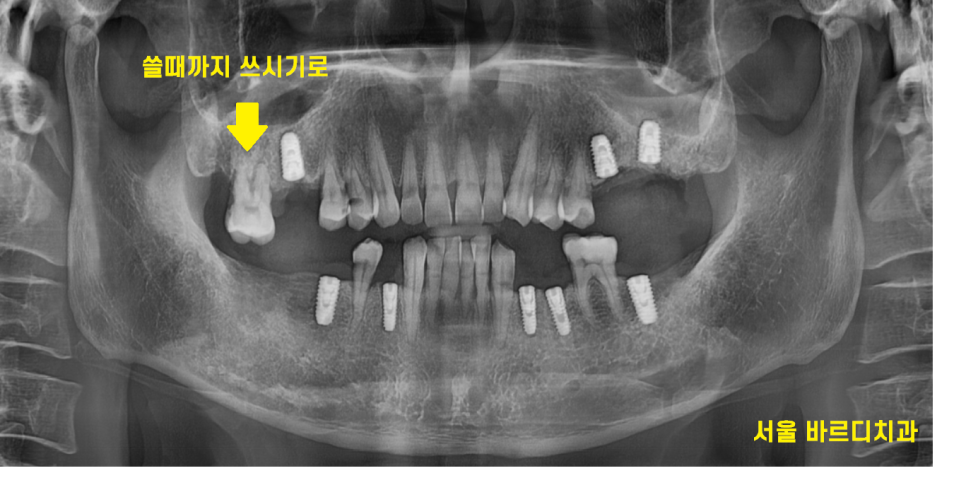

임플란트가 붙을 때까지 충분히 기다리면서

다른 부위도

망월동 치과에서 치료받으셨습니다.

23.01.30

치아가 패인 곳들을 때우고

수술 후 망월동 임플란트 오래 쓰기 위해

양치 방법도 배우시고 말이죠.

시간이 흘러 임플란트 기둥을 세우고

머리를 만들어 드렸습니다.

23.08.18

어금니 빠짐으로 1개 2개씩 물리던 치아가

이제 모두 물리게 해결해 드렸어요~!